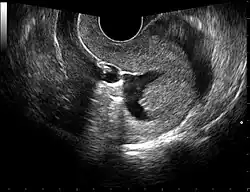

Transvaginal ultrasonography to check the location of an intrauterine device (IUD)

The examination can be performed by transabdominal ultrasonography, generally with a full bladder which acts as an acoustic window to achieve better visualization of pelvis organs, or by transvaginal ultrasonography with a specifically designed vaginal transducer. Transvaginal imaging utilizes a higher frequency imaging, which gives better resolution of the ovaries, uterus and endometrium (the fallopian tubes are generally not seen unless distended), but is limited to depth of image penetration, whereas larger lesions reaching into the abdomen are better seen transabdominally. Having a full bladder for the transabdominal portion of the exam is helpful because sound travels through fluid with less attenuation to better visualize the uterus and ovaries which lies posteriorly to the bladder. The procedure is by definition invasive when performed transvaginally. Scans are performed by health care professionals called sonographers, or gynecologists trained in ultrasound.